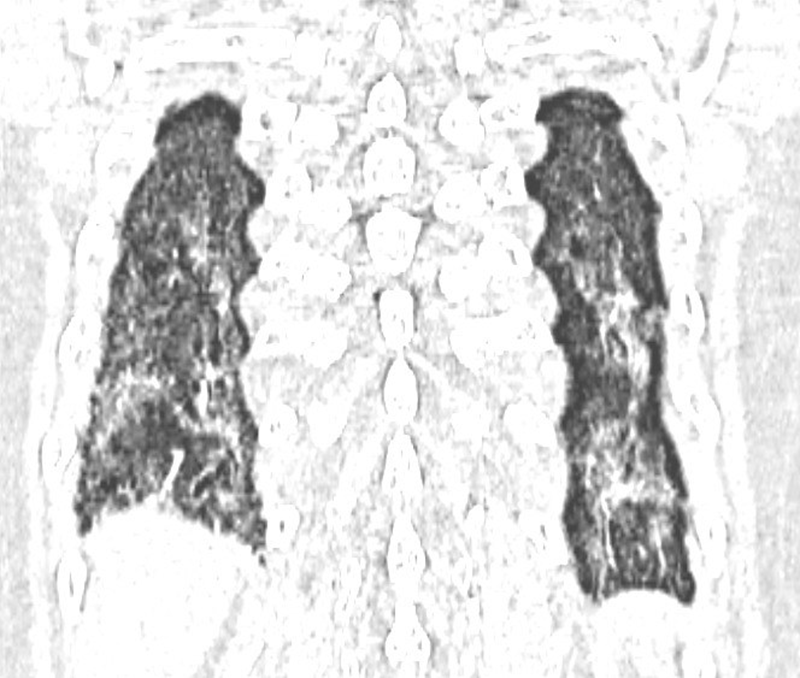

Hình ảnh hai lá phổi xơ hóa